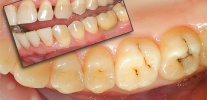

Spesso i denti inferiori della saggezza iniziano a tagliare e ferire, ma non hanno fretta di apparire sulla superficie delle gengive.Nelle immagini è possibile osservare come il dente "saggio" sia quasi in inclinazione orizzontale rispetto a quello adiacente, per cui in alcuni casi clinici inizia anche a provocare dolore. Anche nel dente del giudizio che non è ancora apparso sulla superficie delle gengive, possono verificarsi carie e sue complicazioni, poiché i batteri cariogeni passano facilmente sotto la gomma dietro il penultimo "sette".

I denti del giudizio iniziano a far male, non solo a causa di problemi durante la dentizione, ma anche dopo un'uscita completa o parziale di successo dalle gengive. Non hanno quasi mai un antagonista sul lato opposto, sono troppo distanti nella mascella, spesso al di sotto del livello del settimo dente e, di conseguenza, il loro livello di autopulizia e igiene lascia molto a desiderare. Pertanto, la carie si sviluppa rapidamente sul dente del giudizio, spesso con danni alla camera della polpa, accompagnata da dolore parossistico acuto e sensazioni dolorose di lunga durata da varie sostanze irritanti (pulpite).